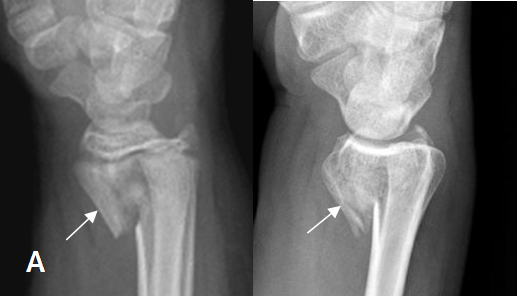

Fig 35. Fractura de Smith.

A y B: Rx lateral. Fractura de Smith, con desplazamiento anterior del fragmento distal del radio.